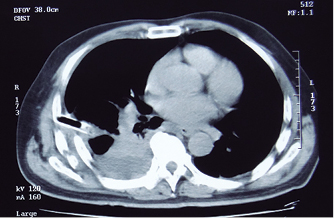

Bajo anestesia general e intubación endotraqueal selectiva se realizó toracotomía posterolateral derecha con apertura del tórax en el 5o espacio intercostal. Se evacuó el hemotórax retenido, luego se practicó decorticación pleural visceral y parietal y finalmente, se procedió a la osteosíntesis de los arcos costales fracturados que provocaron la deformidad con hundimiento de la parrilla costal y lesión del parénquima pulmonar por los extremos de las costillas con proyección intratorácica. Cada foco de fractura fue expuesto levantando el periostio adyacente a la línea de fractura. Se perforó cada arco costal fracturado con un taladro eléctrico y brocas de 2 mm en dos puntos equidistantes en cada extremo del segmento fracturado. Los agujeros se trepanaron a 10 mm de los bordes fracturados con separación de 10 mm, uno por detrás del otro, pero en diferentes líneas (Figura 3). Se pasó el alambre (material sutura no absorbible monofilamento #5 Ethi-Pack, Ethicon) del agujero más lejano (A) de fuera adentro, al más corto (C) de dentro afuera y del corto (B) de fuera adentro; al más lejos (D) de dentro afuera; cerrándolo en la cara externa de la costilla (Figura 4). Usamos un Angiocath # 16 como facilitador del paso del alambre, cuando se pasa del espacio intratorácico hacia el exterior.

Con esta técnica de exposición, fijación y estabilización se alinearon las fracturas de los arcos costales 4o, 5o, 6o y 7o, las que se encontraban más desplazadas hacia el espacio pleural con el resultado esperado, tal como puede verse en la Figura 5. No se requirió estabilización quirúrgica de las fracturas de los arcos costales 3o, 8o y 9o por estar adecuadamente alineadas y no ser un peligro de lesión parenquimatosa. Se colocó tubo intercostal # 32 por incisión contralateral y se cierra por planos. El paciente fue extubado al final del procedimiento y luego de su recuperación anestésica, regresó a su habitación sin pasar por la UCI. Le fueron administrados antibióticos profilácticos, analgésicos y se inició pronto la fisioterapia respiratoria. Egresó al tercer día posoperatorio después del retiro del tubo intercostal. La radiografía posoperatoria muestra la alineación de las fracturas costales, la resolución de la deformidad torácica y la rehabilitación del espacio pleural por el pulmón después de la evacuación del hemotórax retenido (Figura 6).